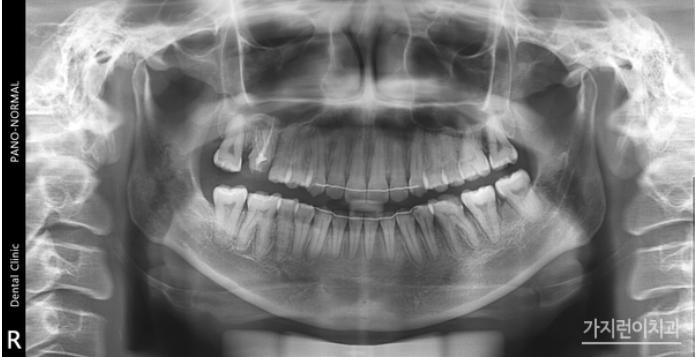

해당 환자분의 경우는 사랑니를 어금니로 대체하는 교정을 계획했었는데요. 위 사진을 보면 사랑니를 세우면서 임플란트를 식립하지 않고 발치 공간을 닫았습니다. 하악 좌측의 사랑니를 효과적으로 세우기 위해 modified bonded cantilever (MBC) spring을 사용했는데요.

상하악 중심선도 잘 맞추었고 교합도 정상교합으로 맞춘 것을 볼 수 있습니다. 하악 사랑니도 잘 세워진 것을 눈으로 확인할 수 있을 정도가 되었는데요. 더 쉽게 보기 위해 교정 전후의 엑스레이 사진도 확인해보겠습니다.

짜잔! 정말 달라졌죠! 사랑니 때문에 치아가 틀어져 치아교정을 고민하는 분들도 계시지만 임플란트 대신 쓰러진 사랑니를 바로 세워 치아교정을 통해 임플란트 대신 사용해볼 수도 있었는데요. 사랑니가 날 공간이 부족하면 앞의 치아들을 다 밀면서 나게 되고 부분적으로 맹출하게 되지만 모양이 괜찮다면 얼마든지 세워서 비어있는 공간을 닫아 어금니로 사용할 수 있답니다. 이를 뽑을 때는 신중해야 하는데요. 사랑니라도 치아를 배열할 공간이 필요하거나 치아를 뒤로 밀어주어야 하는 경우에는 발치하는 게 좋습니다. 참고로 사랑니의 경우 청소년, 청년 시기에 교정치료를 진행할 때 확인하는 경우가 많았는데요. 모양이 이상하거나 추후 문제가 될 것으로 판단이 된다면 25세 이전에 발치하는 것을 권유드리는 편입니다. 그 전에는 맹출된지 얼마 지나지 않아 무르기 때문이에요.